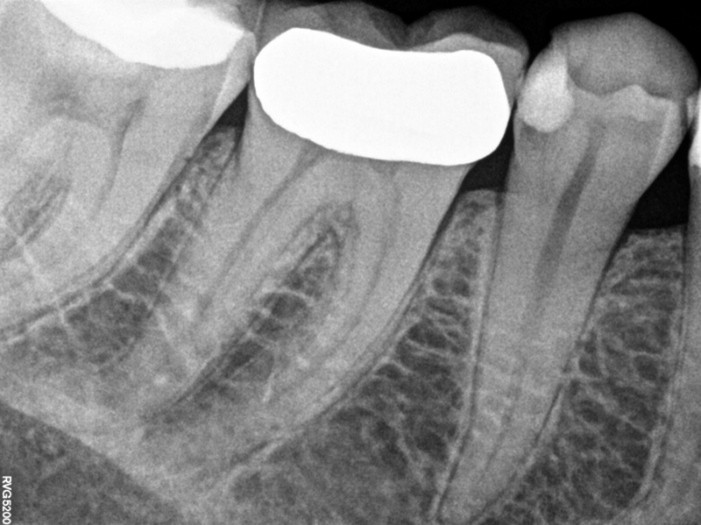

Pre-operative

Post-operative